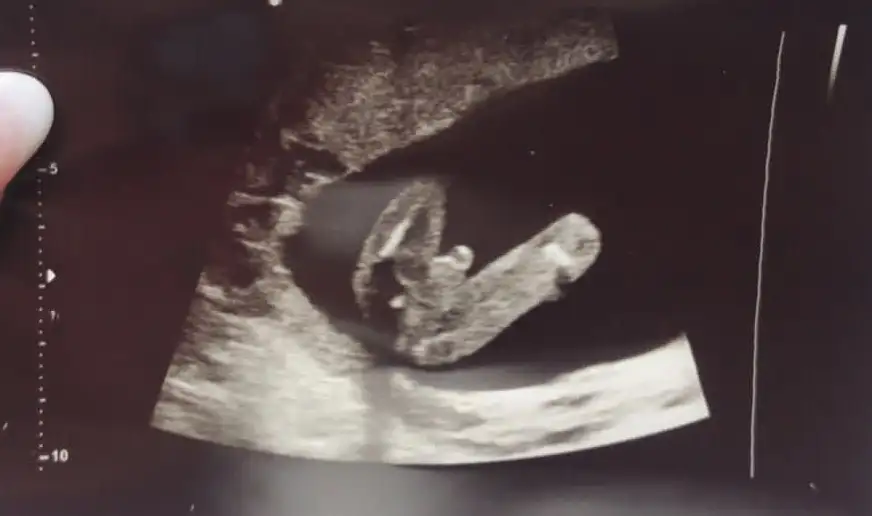

Arkadaşlar selam bizde çok kız bebek istiyorduk 12. Ve 14. Haftalarda doktorumuz kız demişti ama bugun 16.5 haftalık kontrolümüzde yanıldım diyerek erkek olduğunu söyledi ultrason fotoğraflarını paylaşıyorum ne düşünüyosunuz